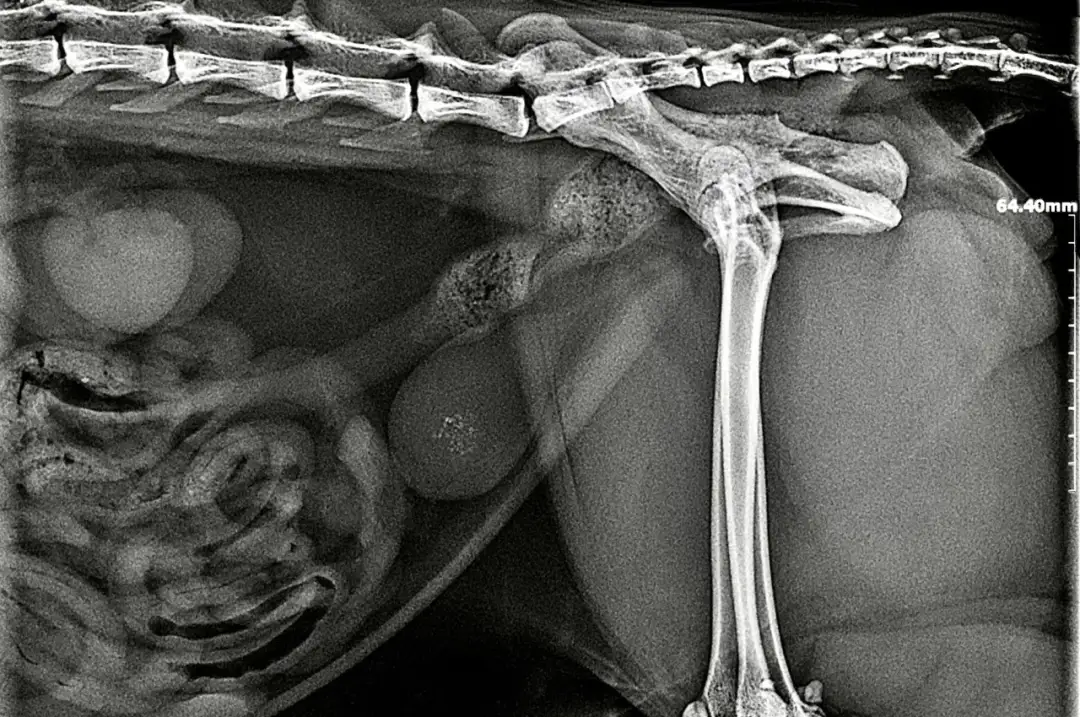

Obraz pęcherza: kiedy potrzebne jest USG lub RTG?

W niektórych przypadkach sama analiza moczu może nie wystarczyć do postawienia pełnej diagnozy. Jeśli weterynarz podejrzewa obecność kamieni moczowych, może zlecić badania obrazowe. Ultrasonografia (USG) jamy brzusznej pozwala na dokładne uwidocznienie pęcherza moczowego i zlokalizowanie ewentualnych kamieni, ocenę ich wielkości oraz stanu ściany pęcherza. Rentgen (RTG) jest również pomocny, ponieważ kamienie struwitowe są widoczne na zdjęciach rentgenowskich. Badania obrazowe pomagają weterynarzowi ocenić skalę problemu i zaplanować odpowiednie leczenie.